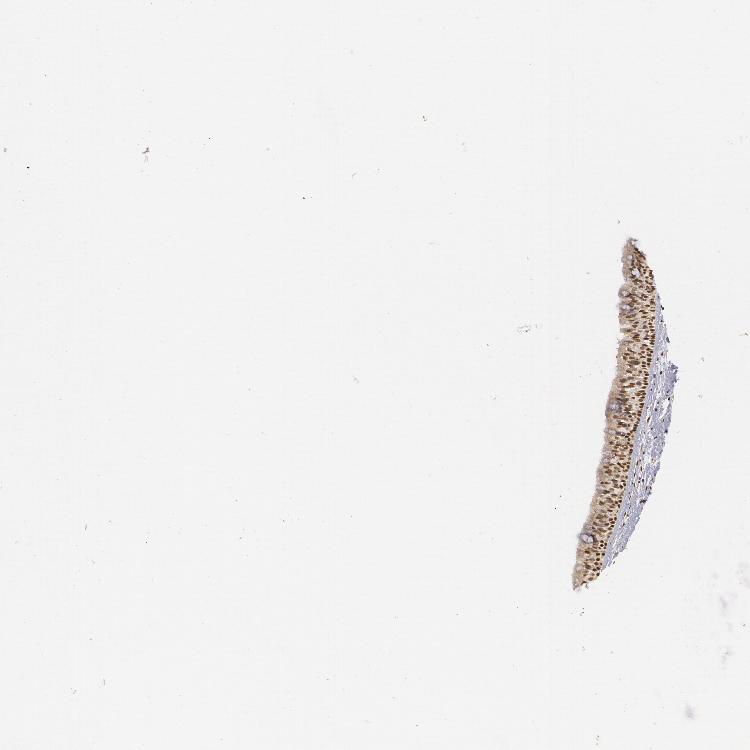

TISSUE PRIMARY DATA NASOPHARYNX Show tissue menu

NASOPHARYNX - Antibody stainingi

Antibody staining in the annotated cell types in the current human tissue is reported as not detected, low, medium, or high, based on conventional immunohistochemistry profiling in selected tissues. This score is based on the combination of the staining intensity and fraction of stained cells.

Each image is clickable and will lead to virtual microscopy that enables deeper exploration of all samples and also displays staining intensity scores, fraction scores and subcellular localization as well as patient and tissue information for each sample.

Antibody CAB002003

Respiratory epithelial cells High